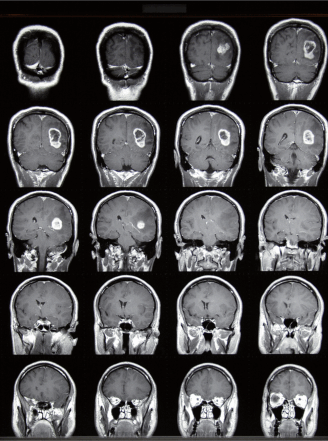

Get Brain Cancer Test Name Pictures. In case of symptoms or an abnormal screening test, more testing can help find out what it is. This helps evaluate the tumor in order to develop a a multidisciplinary team of experts uses a variety of tests and tools for diagnosing brain cancer, evaluating the disease and customizing a treatment plan.

Additional tests are needed to confirm a cancer cancer blood tests and other laboratory tests may help your doctor make a cancer diagnosis. Brain tumors alone may be cancerous or non cancerous. Guideline from the college of american. In case of symptoms or an abnormal screening test, more testing can help find out what it is.